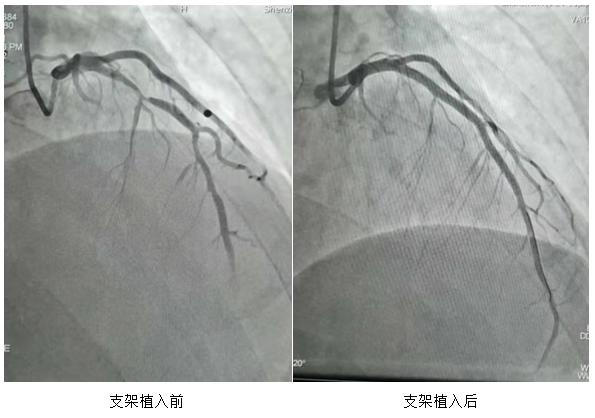

心血管内科主任陈海波主任医师仔细了解病情 , 决定介入手术治疗 。 冠脉造影发现梗死血管是左前降支 , 在最狭窄的部位植入一枚进口支架后 , 血管内超声检查发现支架以远的中段 , 以及前降支近段还有明显斑块 , 又植入2枚国产支架 , 后扩张整形 , 血管内超声波多次检查 , 证实支架贴壁非常满意 , 没有夹层 。

血管内超声检查 , 支架植入后